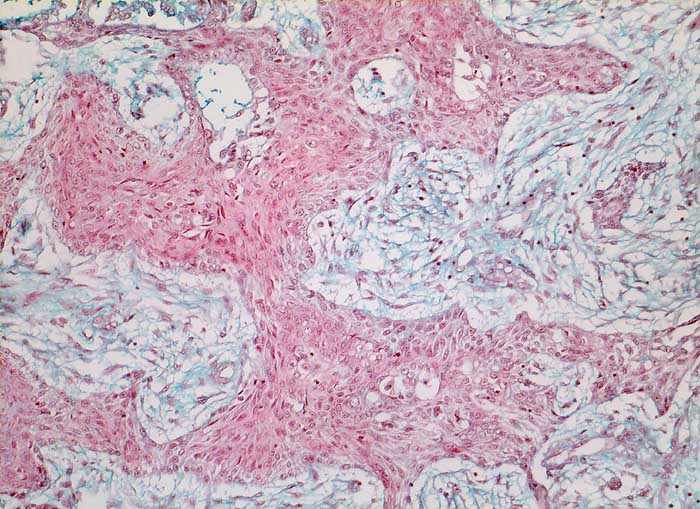

Verhornende Plattenepithelkarzinome sind charakterisiert durch mehr einzeln gelagerte Zellen mit deutlicher Pleomorphie, das Zytoplasma ist dicht und orangeophil. Die Kerne sind pyknotisch oder erinnern an Lavabrocken.

Die häufigeren nicht verhornenden Plattenepithelkarzinome bilden eher Verbände. Die Tumorzellen sind uniformer, das dichte Zytoplasma ist blau-grün gefärbt und scharf begrenzt. Die Zellkerne sind hyperchromatisch und enthalten grosse Nukleolen. Die Abgrenzung des nicht verhornenden Plattenpithelkarzinoms vom Adenokarzinom kann schwierig sein. In der Regel ist das Kernchromatin der Plattenepithelkarzinome dichter und die Nukleolen weniger prominent.

Die Abbildungen zeigen ein verhorntes und ein unverhorntes Plattenepithelkarzinom zum Vergleich.